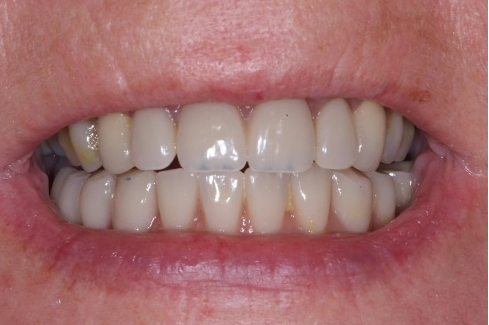

An example of one of the first cases that we did this way is below, including the most recent images of the case.

This illustrates the power of guided surgery and constant improvement.

When we jump forward to where we are now, 12 years later, so much has changed with how we provide our implant dentistry.

Dare I say it, this is the sum of the aggregation over the years of all of our marginal gains.

Here is a more recent case…

Not only have we honed our techniques and are using the better, modern equipment available to us, but our systems and processes allow us to work smarter, not harder.

In turn, this leaves us time to focus on working on the next one per cent improvement.